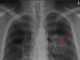

Naše plíce regenerovat určitě umí, umí regenerovat stejně jako další tkáně, nemůžeme si to představit, že by nám dorostly plíce jak ještěrce, kdybychom usekli ocásek, ale regenerace tam určitě je, takže i po těžkých zápalech plic vidíme krásnou regeneraci. Viděli jsme třeba pacienty po těžkém covidu, kdy jsme si udělali cétéčko, tak ty plíce na tom cétéčku byly úplně bílé, když to tak řeknu, a dneska pacienti nemají v podstatě žádné následky.